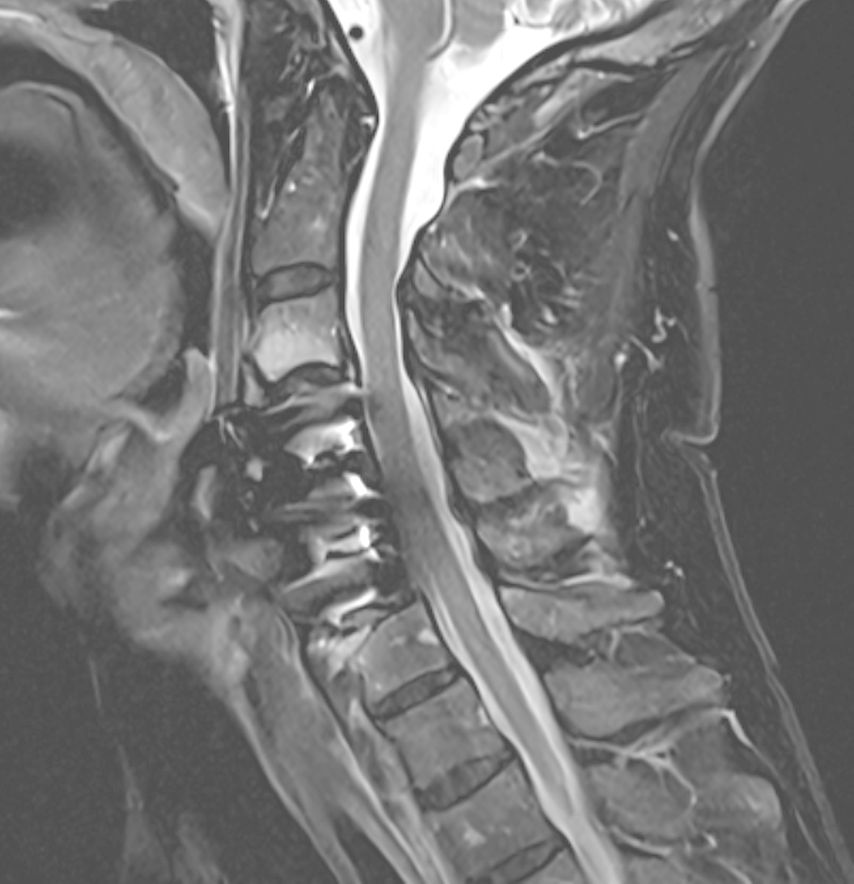

Die Navigation stellt nicht nur beim Einbringen von Implantaten eine Hilfe dar, sondern kann auch in anatomisch herausfordernden Situationen rein zur Verbesserung der Orientierung zu Hilfe genommen werden. Mögliche Anwendungsfelder stellen hier beispielsweise die untere HWS oder der zervikothorakale Übergang dar, welche im konventionellen Röntgen teilweise schwer darstellbar sind. Abbildung 16 zeigt den MR-Befund einer 32-jährigen Patientin, die auswärtig zur ACDF C6/7 indiziert wurde, wobei der Eingriff dort aber aufgrund der Unmöglichkeit, die HWS unter Durchleuchtung entsprechend einzustellen, nicht erfolgte. Abbildung 17 zeigt das intraoperative Röntgen mit bereits kräftigem Schulterzug, in dem aber nur mehr das Segment C4/5 sicher beurteilt werden kann. In diesem Fall erfolgte mittels O-Arm der Eingriff navigiert. Ein anderes Beispiel ist die Anwendung zur Orientierung bei Osteotomien, wo die Navigation an unserer Klinik ebenfalls standardmäßig angewendet wird. Abbildung 18 zeigt einen intraoperativen Screenshot im Rahmen der Navigationsanwendung bei einer thorakalen Corporektomie (Th12) von dorsal im Rahmen einer Tumorresektion. Auch bei verkalkten Bandscheibenvorfällen, wie in Abbildung 19 dargestellt, kann die Navigation zur besseren intraoperativen Orientierung herangezogen werden. Ein weiteres Beispiel der vielfältigen Anwendungsmöglichkeiten der Navigation zeigt Abbildung 20. In diesem Fall wurde im Rahmen einer C1/2-Verschraubung nach Harms das Gelenk C1/2 beidseits navigiert zur besseren Fusion angefrischt.